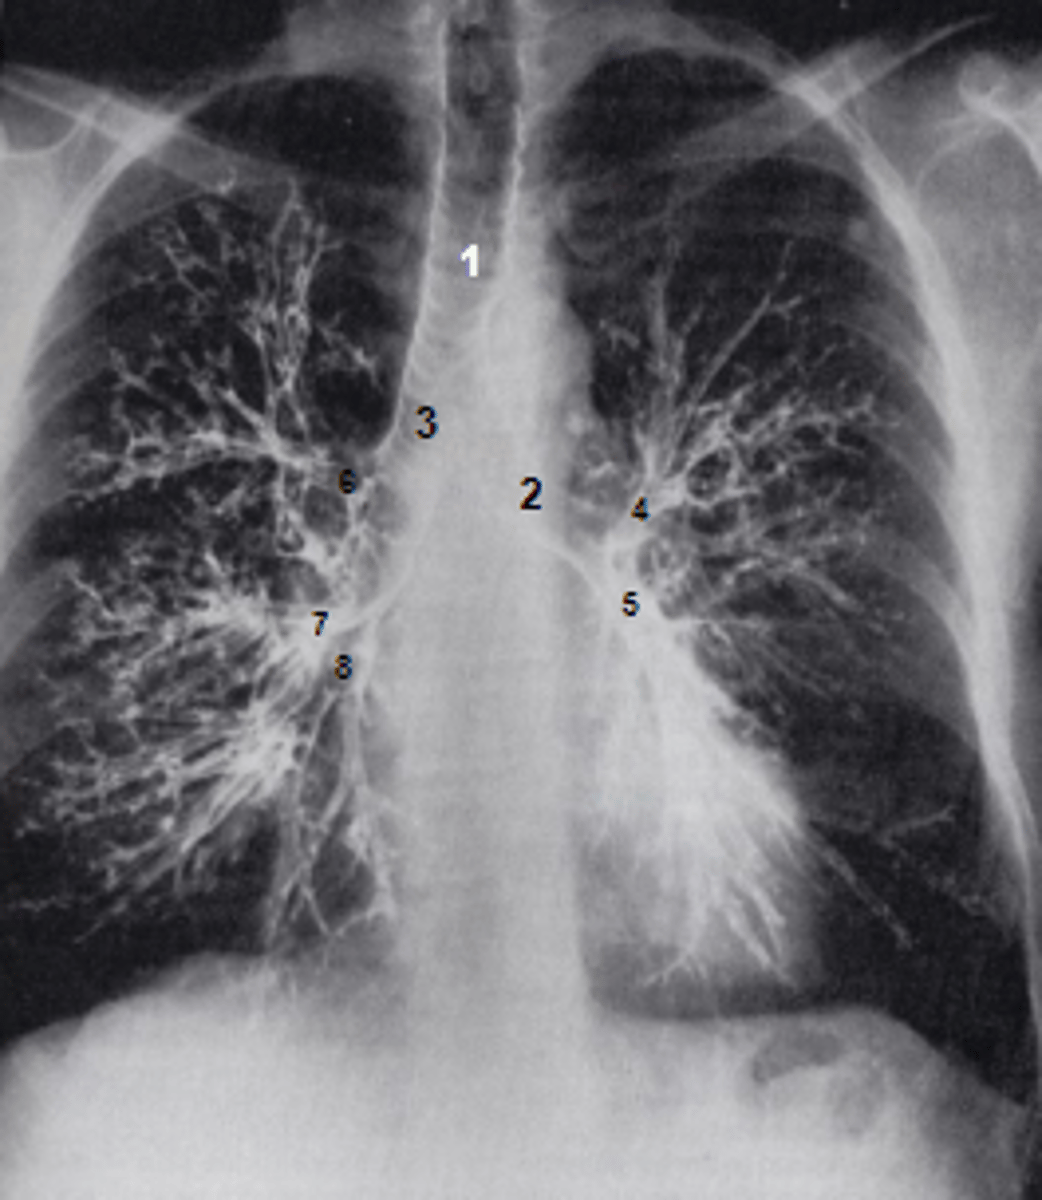

1

at what number is the trachea

2

at what number is the left main bronchus

3

at what number is the right main bronchus

4

at what number is the left superior lobar bronchus

5

at what number is the left inferior lobar bronchus

6

at what number is the right superior lobar bronchus

7

at what number is the right middle lobar bronchus

8

at what number is the right inferior lobar bronchus